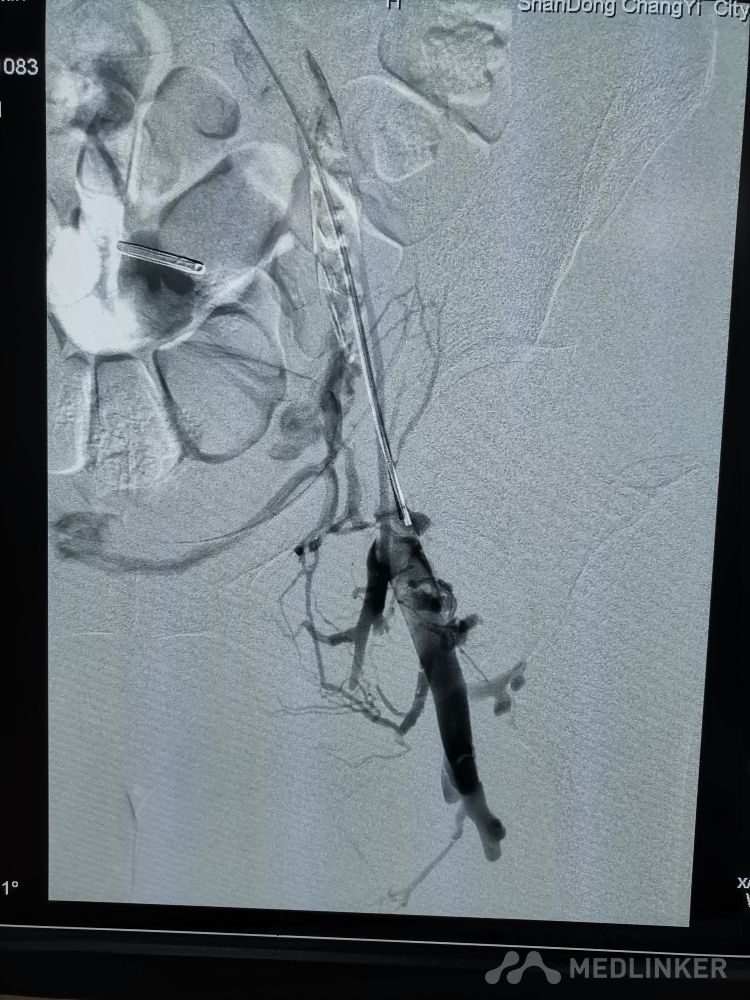

重视髂静脉压迫综合征。不同的临床表现,相同的病因,均为髂静脉压迫所致。第一例,表现为下肢静脉曲张伴溃疡,造影证实,髂静脉支架置入后解决。第二例,表现为左侧髂股静脉血栓,置管溶栓并髂静脉支架置入开通血管。第三例,下肢深静脉血栓后遗症,外院已行髂静脉支架置入,但皮肤营养情况仍持续加重,开通股浅 ,可见病变局部异常坚硬。精准施治,对症下药。